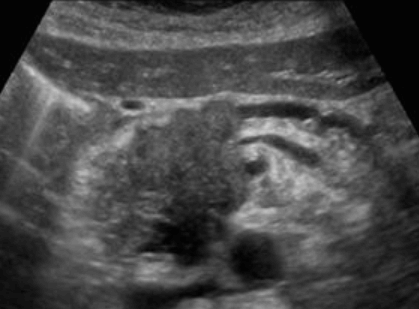

Choledocholithiasis US finding

- 총담관 내에 후방음향음영을 동반한 강한 에코가 관찰된다.

- 총담관의 확장 소견이 보인다. ( 7mm 이상)

- 담석이 관찰되지 않고 간외, 간내담관의 확장소견을 시사하는 엽총징후(shotgun sign)이나 평행관 징후(parallel channel sign)가 관찰되기도 한다.

- 엽총징후(shotgun sign): 간외 담관이 확장되어 간외 담관과 문맥이 이웃해 관찰된다.

- 평행관 징후(parallel channel sign): 간내 담관이 확장되어 인접하고 있는 문맥과 나란히 2개의 관상구조로 나타난다.